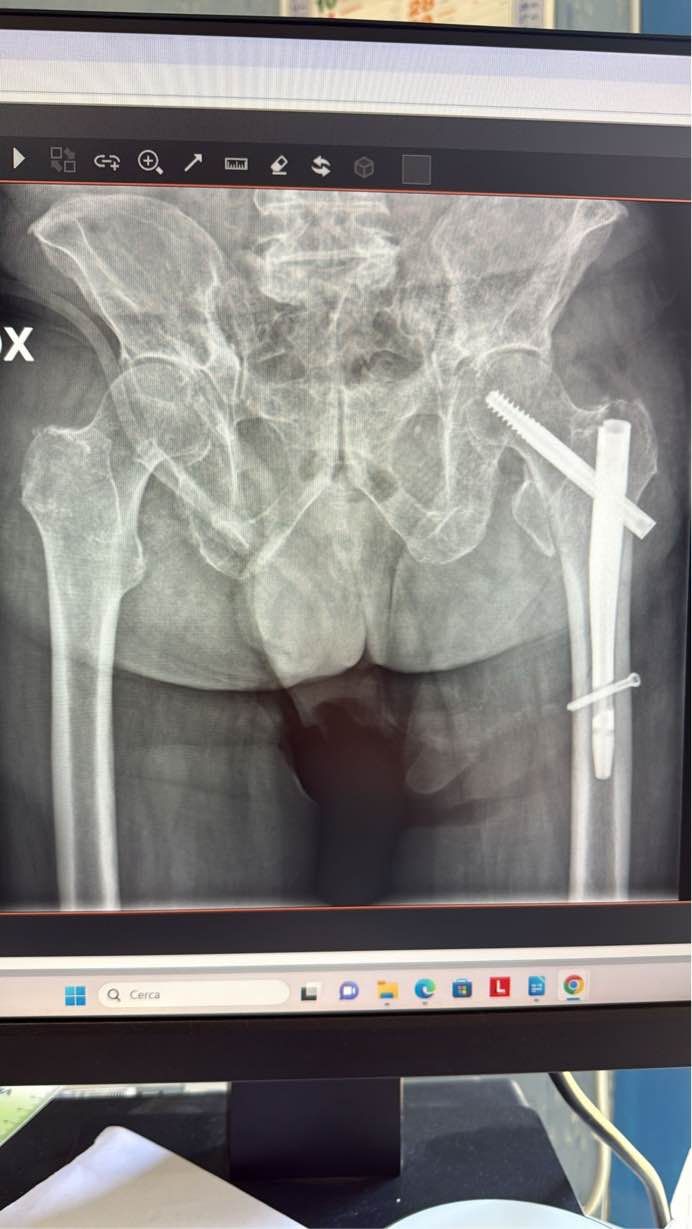

Ho conseguito la specializzazione in Ortopedia e Traumatologia presso l'Università di Palermo nel 2006 con il massimo dei voti. Successivamente ho lavorato presso l'Ospedale Fatebenefratelli - Buccheri la Ferla di Palermo, per poi trasferirmi presso l'ASP di Trapani, dove sono stato Dirigente Medico presso il Presidio Ospedaliero Vittorio Emanuele II di Castelvetrano. Oggi sono Dirigente Medico di primo livello presso l'Unità Operativa Complessa di Ortopedia e Traumatologia del Presidio Ospedaliero di Partinico, dove svolgo attività di ambulatorio, di reparto, eseguo interventi chirurgici di traumatologia e in elezione (protesi di anca e di ginocchio, interventi correttivi di alluce vago, dita in griffe, borsiti, sindrome del tunnel carpale, dito a scatto, sindrome di De Quervain e altro).

Mi occupo di Chirurgia Ortopedica Protesica all'anca e al ginocchio .